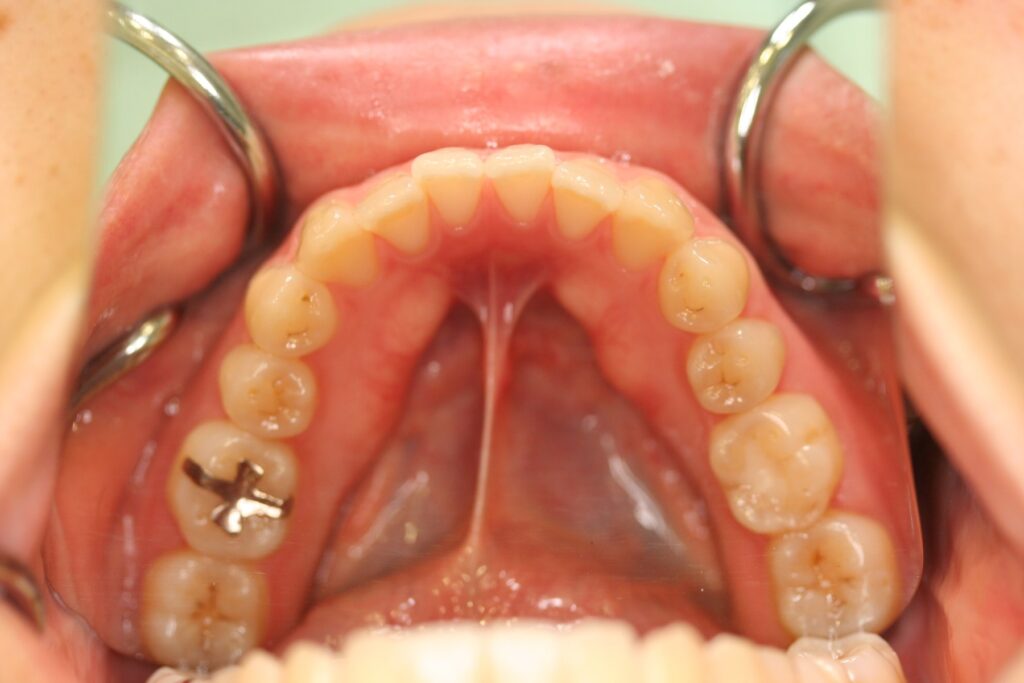

治療実績(症例) アライナー矯正 症例1 上顎前突症例 症例2 上下顎前突症例 症例3 叢生 症例4 開咬 症例5 開咬(外科的矯正治療) アライナー矯正 Post Share Hatena Line RSS feedly Pin it note 1.主訴2.診断名3.初診時年齢4.治療に用いた主な装置とオプション5.抜歯部位6.治療期間・通院回数7.総額と費用内訳総額相談検査・診断料調整料4,000円8.リスク・副作用 治療前 治療中 治療後